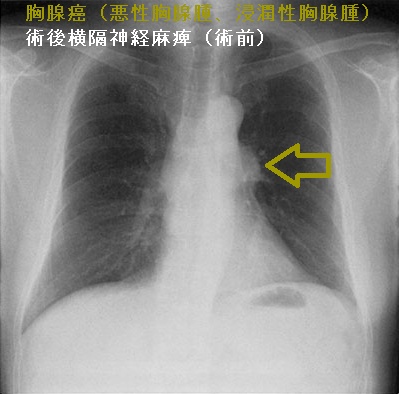

胸腺癌(悪性胸腺腫、浸潤性胸腺腫)

胸腺癌(悪性胸腺腫、浸潤性胸腺腫)は非常に稀で、標準的な治療が存在しません。組織型も、扁平上皮癌・未分化癌・小細胞癌と多様です。甲状腺機能亢進症/バセドウ病に合併した

長崎甲状腺クリニック(大阪)では甲状腺機能低下症/橋本病に合併した胸腺癌(悪性胸腺腫、浸潤性胸腺腫)の自験例があります。

胸腺癌(悪性胸腺腫、浸潤性胸腺腫)は前胸部から肺門部まで浸潤し、横隔神経自体にも浸潤するため、摘出手術で横隔神経を損傷する可能性が高い(術後横隔神経麻痺)。術後横隔神経麻痺では、術後から息が深く吸えなくなります。内肋間筋・補助呼吸筋と代償性の呼吸数増加で補える場合が多いが、重症例は胸腔鏡下横隔膜縫縮術の適応。